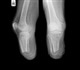

In addition to the Phase 2 results, the company's successful preclinical studies of luliconazole in onychomycosis (fungal infections of the nail) demonstrate that it has the ability to easily penetrate toenails achieving rapid fungal eradication in the nail bed, as measured by MedPharm's in vitro ChubTur® infected nail model. TOPICA plans to file an IND for onychomycosis before the end of 2009. Onychomycosis affects approximately 35 million people in the U.S. The disease can cause extreme disfigurement of nails and can often result in pain. The potential annual U.S. market for onychomycosis treatment is estimated at $3.0 billion. The utility of currently approved oral therapies for onychomycosis are limited by their side effect profile and the approved topical therapy has minimal efficacy.